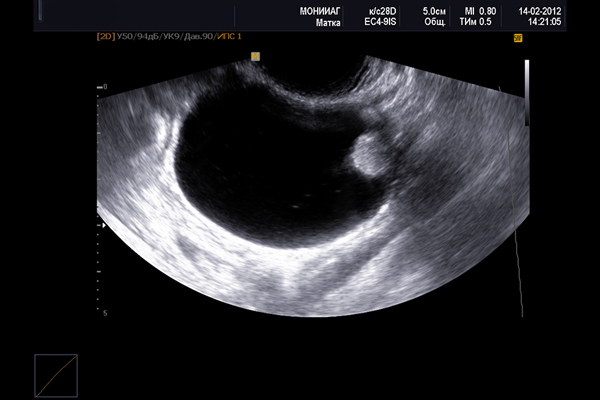

- УЗИ органов малого таза (помогает выявить опухоль от 3-х см с плотной гладкой капсулой, для нахождения более мелкой кисты следует использовать трансвагинальный датчик);

На фото ниже показано, как киста выглядит на УЗИ.